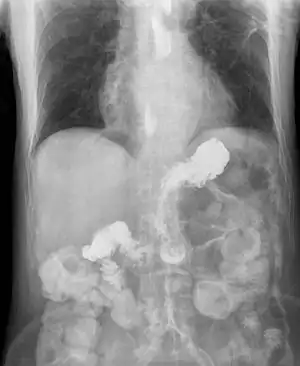

![]() Рентгеноскопічна картина важкого гастроезофагеального рефлюксу. Сульфат барію, введений через гастростому в шлунок, швидко проникає у стравохід через розслаблений нижній сфінктер стравоходу. Рентгеноскопічна картина важкого гастроезофагеального рефлюксу. Сульфат барію, введений через гастростому в шлунок, швидко проникає у стравохід через розслаблений нижній сфінктер стравоходу. | |

Важливим методом діагностики гастроезофагеальної рефлюксної хвороби є рентгенологічне обстеження стравоходу. Хоча рентгеноскопія не має самостійного значення в діагностиці ГЕРХ, а лише дає змогу зафіксувати епізоди рефлюксу, наявність яких не підтверджує, а відсутність не виключає ГЕРХ, та не є достатньо чутливим та специфічним для діагностики запалення стравоходу, рентгеноскопія є найбільш інформативним методом для діагностики кили стравохідного отвору діафрагми та допомагає у диференційній діагностиці з іншими хворобами стравоходу (ахалазії кардії, дивертикулів, стриктур та інших захворювань), особливо у виключенні інфільтративних форм раку стравоходу, який не виявляється під час ендоскопічного та морфологічного дослідження.[9][20] Рентгенологічне обстеження має вирішальне значення при виборі об'єму і тактики хірургічного лікування анатомічних порушень у ділянці з'єднання стравоходу зі шлунком.[10]